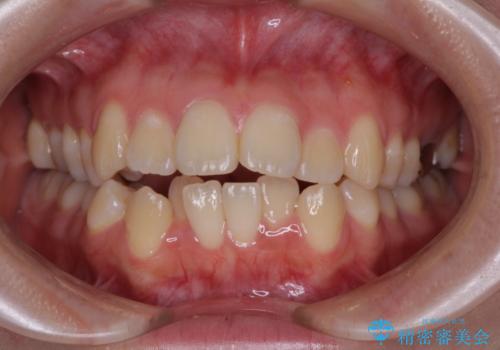

- 下の前歯のデコボコと、口元の突出感を改善したいと来院された患者様です。

上下左右の第一小臼歯を抜歯して、目立ちにくいワイヤー装置で矯正を行いました。